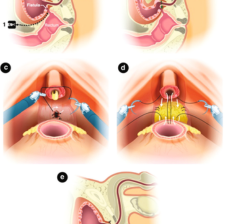

Sphincter Repair for Incontinence

This procedure repairs a damaged or weakened anal sphincter that occurred during childbirth. Doctors identify an injured area of muscle and free its edges from the surrounding tissue. They then bring the muscle edges back together and sew them in an overl